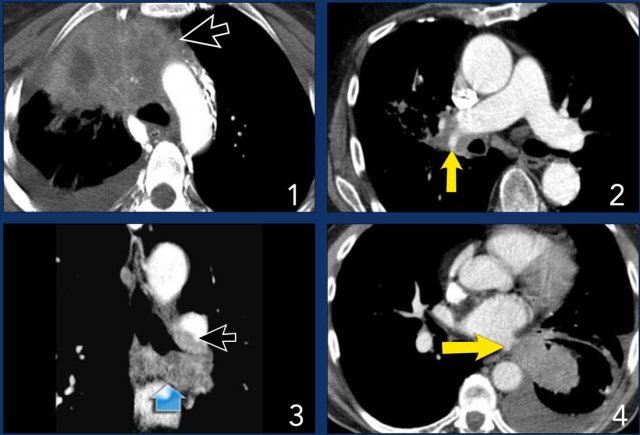

T4 tumor

1. A typical T4 tumor in the right upper lobe with invasion of the mediastinum.

2. Invasion of the right pulmonary artery.

3. Invasion of the carina.

4. Invasion of the left atrium.